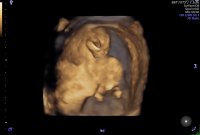

Fikk veldig fine bilder i dag! Fortsatt sprellete, men ikke så mye som sist hehe. Gyn mente ho også er godt over 90% sikker på kjønn. Fikk det i en konvolutt for å åpne med mannen senere:D

13+0 etter mens, målt til 13+6. Blir nok en februarbebis på oss!